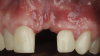

The patient in this case had undergone implant therapy at the site of tooth No. 9 and was restored with a cement-retained restoration more than 5 years prior. At presentation, the site demonstrated a peri-implant soft-tissue dehiscence that extended approximately 3-mm apical to the gingival margin of tooth No. 8. Thin and erythematous marginal tissue was evident at the zenith (Figure 2). The crown was removed, and a partial thickness flap was reflected using a papilla-sparing incision design. This revealed that the implant was positioned too far facially and that its body was visible through a very thin layer of bone (Figure 3 and Figure 4). The first objective of treatment was to minimize the facial extent of the emerging abutment and crown. To accomplish this, the facially positioned abutment and implant crown margin were both recontoured. The second treatment objective was to provide additional supracrestal soft tissue that would more adequately maintain the peri-implant margin. The tuberosity was selected as a donor site due to its dense, high-quality connective tissue, low propensity for shrinkage, and association with minimal patient discomfort. Once the graft was secured (Figure 5 through Figure 7), the flap was coronally positioned (Figure 8). After a healing period of 2 weeks, the margin of tooth No. 9 exhibited an ideal position in relation to its contralateral counterpart and demonstrated increased soft tissue thickness (Figure 9). Three months postoperatively, further healing had improved the esthetics and the position of the margin had been maintained (Figure 10).

(3.) The crown was removed, and a partial thickness flap was reflected using a papilla-sparing incision design, which revealed that the implant was positioned too far facially and that its body was visible through a very thin layer of bone.

Figure 3

(4.) The crown was removed, and a partial thickness flap was reflected using a papilla-sparing incision design, which revealed that the implant was positioned too far facially and that its body was visible through a very thin layer of bone.

Figure 4